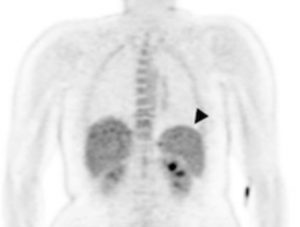

En la imagen por PET se observa el aumento de la captación de la glucosa en el brazo después de la infección por malaria.